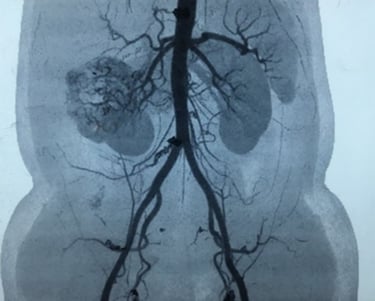

Renal Angiography – is an imaging test to look at the arteries in your kidneys. This is important prior to surgery. This facilitates the urooncologist surgeon to dissect and trace the arteries and veins of kidney but also educates about the feeding tumour vessels. This can be done by conventional Angiography or CT Renal Angiography.